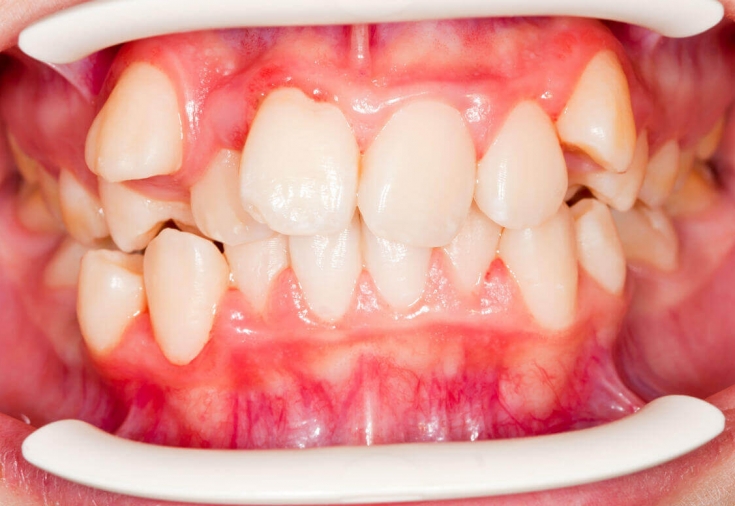

Неправильне положення зуба у зубному ряду називається дистопією. Дистопований зуб може бути зміщений за межі альвеолярного відростка щелепи. Таке становище зуба ускладнює прорізування і зростання сусідніх зубів, крім того, створює значний косметичний дефект. Найчастіше дистопованим зубом виступає третій моляр («зуб мудрості»), верхні та нижні ікла.

Однією з найчастіших причин дистопії зубів є неправильне формування зачатків зубів у період ембріогенезу. Дистопія з'являється при різкому порушенні пропорції розмірів молочних та постійних зубів, при ранньому видаленні тимчасових зубів, при частковій адентії, а також при порушенні послідовності та термінів прорізування зубів.

При невідповідності розмірів щелепи людини та величини її зубів також можуть з'являтися дистоповані зуби. Таке зустрічається у дітей, які успадковують від одного з батьків велику величину зубів, а від іншого з батьків маленький розмір щелепи.

Дистопований зуб заважає нормальному прорізуванню зубів, що сприяє розвитку неправильного прикусу. До того ж, дистопований зуб пошкоджує та травмує тканини губ, язика та щік, що закінчується формуванням декубітальних виразок.

Дистопований зуб не дозволяє здійснити адекватну гігієну порожнини рота, провести процедуру видалення харчових залишків та зубного нальоту. Над частиною дистопованих і ретинованих зубів, що прорізається, часто формуються ясенові кишені. У них накопичуються мікроорганізми та залишки їжі, які призводять до розвитку запального процесу та перикороніту.